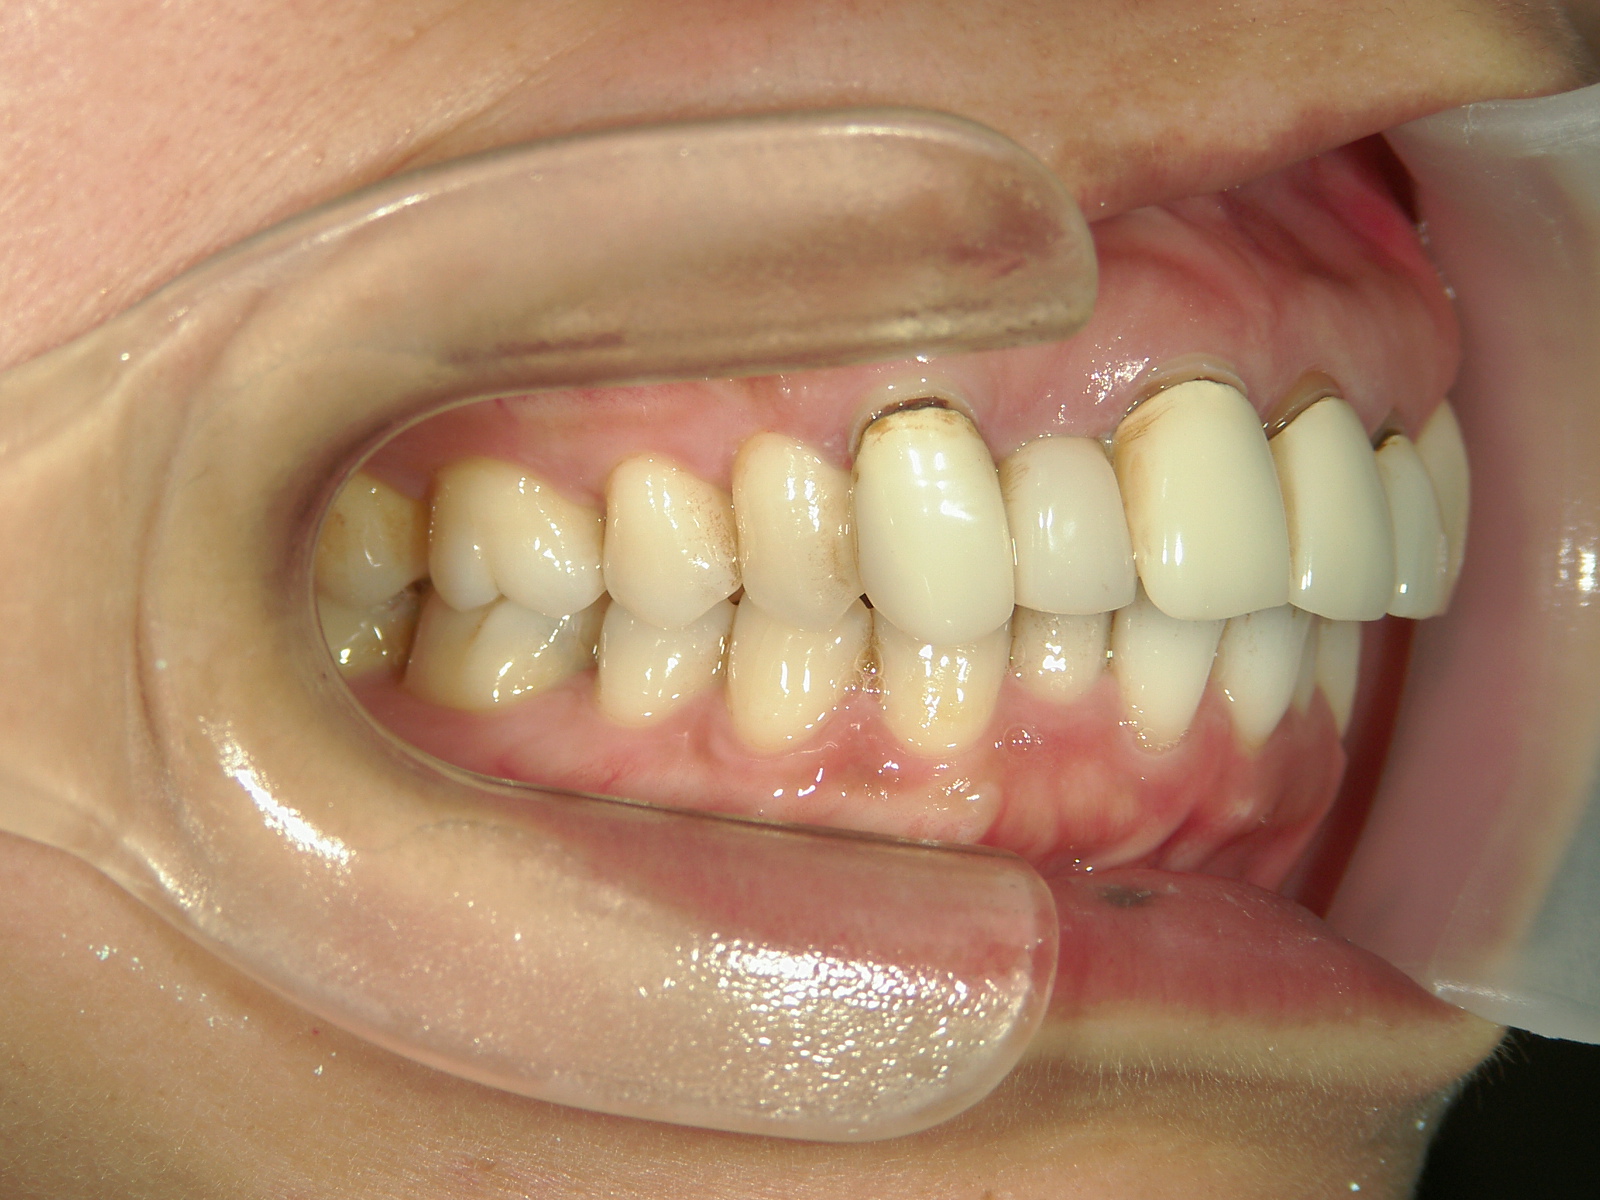

全顎ワイヤー矯正 症例(82)

主訴: 前歯の歯並びが気になる。

上下左右 第一小臼歯(4本)、左右上 親不知(2本)を抜歯。

ミニインプラント、アップライトスプリングを併用。

矯正前に左右上前歯4本を仮歯に変え、矯正治療後にセラミック(SHT)に冠せなおしました。

カテゴリー : ガタガタ(叢生)